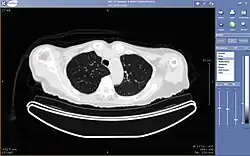

A picture archiving and communication system (PACS) is a medical imaging technology which provides economical storage and convenient access to images from multiple modalities (source machine types).[1] Electronic images and reports are transmitted digitally via PACS; this eliminates the need to manually file, retrieve, or transport film jackets, the folders used to store and protect X-ray film. The universal format for PACS image storage and transfer is DICOM (Digital Imaging and Communications in Medicine). Non-image data, such as scanned documents, may be incorporated using consumer industry standard formats like PDF (Portable Document Format), once encapsulated in DICOM. A PACS consists of four major components: The imaging modalities such as X-ray plain film (PF), computed tomography (CT) and magnetic resonance imaging (MRI), a secured network for the transmission of patient information, workstations for interpreting and reviewing images, and archives for the storage and retrieval of images and reports. Combined with available and emerging web technology, PACS has the ability to deliver timely and efficient access to images, interpretations, and related data. PACS reduces the physical and time barriers associated with traditional film-based image retrieval, distribution, and display.

Typically a PACS consists of a multitude of devices. The first step in typical PACS systems is the modality. Modalities are typically computed tomography (CT), ultrasound, nuclear medicine, positron emission tomography (PET), and magnetic resonance imaging (MRI). Depending on the facility's workflow most modalities send to a quality assurance (QA) workstation or sometimes called a PACS gateway. The QA workstation is a checkpoint to make sure patient demographics are correct as well as other important attributes of a study. If the study information is correct the images are passed to the archive for storage. The central storage device (archive) stores images and in some cases reports, measurements and other information that resides with the images. The next step in the PACS workflow is the reading workstations. The reading workstation is where the radiologist reviews the patient's study and formulates their diagnosis. Normally tied to the reading workstation is a reporting package that assists the radiologist with dictating the final report. Reporting software is optional and there are various ways in which doctors prefer to dictate their report. Ancillary to the workflow mentioned, there is normally CD/DVD authoring software used to burn patient studies for distribution to patients or referring physicians. The diagram above shows a typical workflow in most imaging centers and hospitals. Note that this section does not cover integration to a Radiology Information System, Hospital Information System and other such front-end system that relates to the PACS workflow.